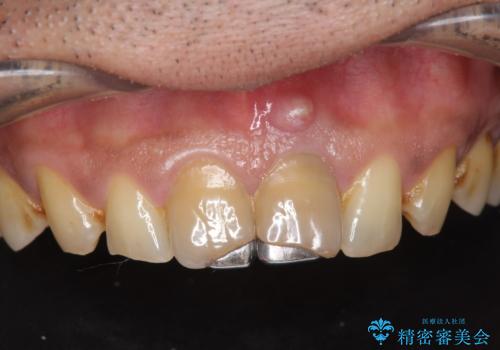

[ジルコニアクラウン治療] 笑った時に目立つ銀歯を白くしたい

![[ジルコニアクラウン治療] 笑った時に目立つ銀歯を白くしたいの症例 治療後](https://seimitsushinbi.jp/wp/wp-content/uploads/2020/07/b5a325afedd469212bae5e25910ae923-500x350.jpg?v=1595071338)